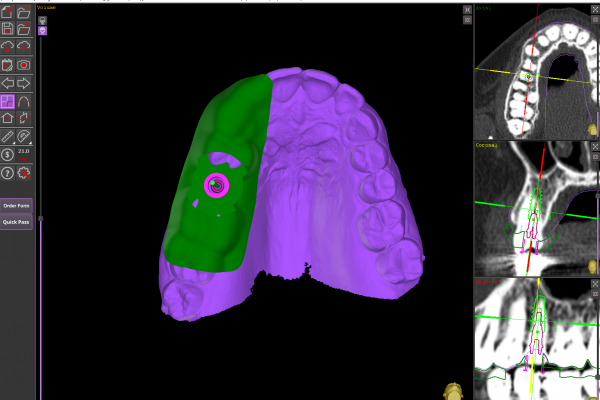

Cirugía Guiada por Ordenador

En nuestra clínica, ofrecemos cirugía guiada utilizando software 3D exacto, una técnica innovadora que nos permite planificar con precisión la colocación de los implantes y asegurar su correcta integración en el hueso maxilar o mandibular. De esta manera, podemos garantizar una colocación precisa, sin errores y con un mínimo de molestias para el paciente.

Durante la cirugía, se utilizan guías quirúrgicas personalizadas basadas en esta planificación digital. Estas guías ayudan a posicionar el implante en el lugar exacto determinado en la planificación, asegurando que esté perfectamente alineado y rodeado de suficiente hueso, lo cual es crucial para su integración y estabilidad a largo plazo. Además, esta precisión garantiza que el implante esté en la posición óptima para recibir la prótesis dental, lo que mejora la funcionalidad y estética del resultado final.